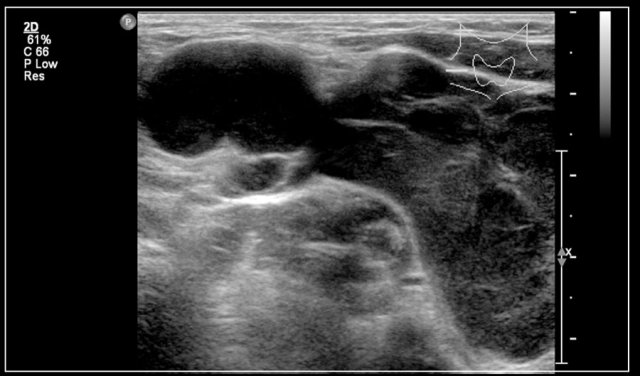

Here an ultrasound image of a six-year-old girl with a sudden swelling in the left neck.

There were several small anechoic cysts and one large cyst containing internal echoes, which were probably the result of a bleeding in a preexistent lymphangioma.

A 3-year-old boy presented suddenly with a supraclavicular mass.

Ultrasound showed a lesion with echogenic debris.

A hemorrhage in a preexisting lymphangioma was suspected.

Continue with the MRI.

The T1-weighted image shows a slightly hyperintense lesion with a fluid-fluid level (arrow).

After gadolineum administration there is enhancement of the cyst wall.

The lesion subsided with conservative therapy.